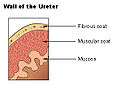

The ureter is surrounded by urothelium, a type of transitional epithelium that is capable of responding to stretches in the ureters. The transitional epithelium may appear as a columnar epithelia when relaxed, and squamous epithelia when distended. Below the epithelium, a Lamina Propria exists. The Lamina Propria is made up of loose connective tissue with many elastic fibers interspersed with blood vessels, veins and lymphatics. The ureter is surrounded by two muscular layers, an inner longitudinal layer of muscle, and an outer circular or spiral layer of muscle.[5]:324

View of the ureter under the microscope

View of the ureter under the microscope Wall of the ureter

Wall of the ureter